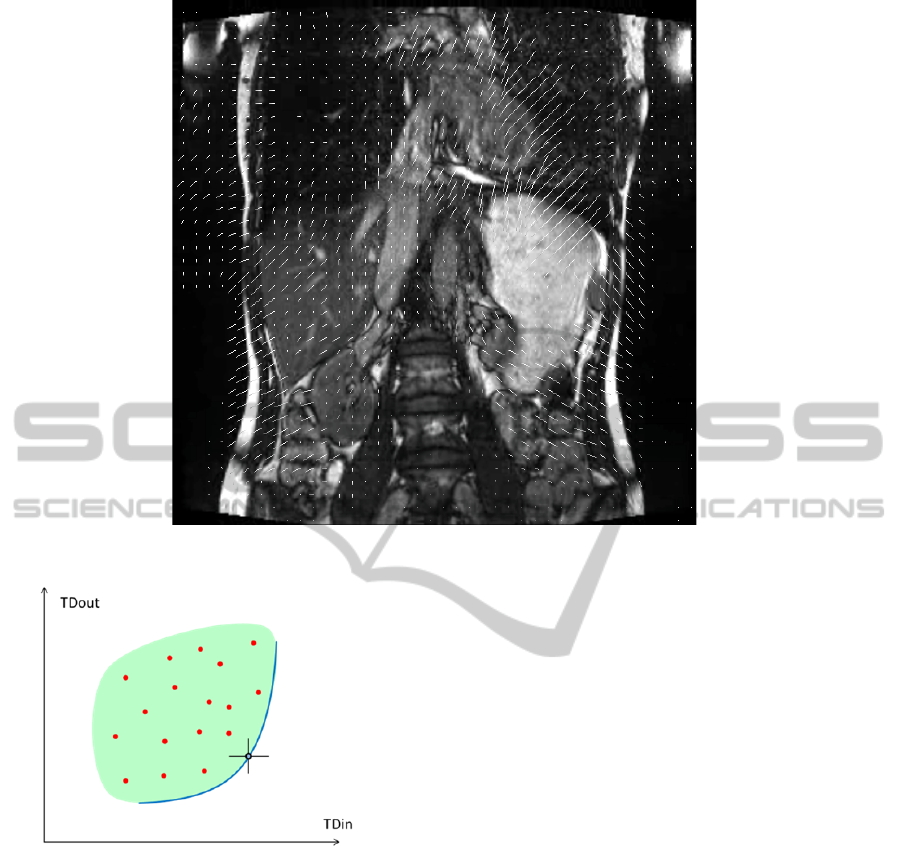

The purpose of therapy planning is a

maximization of thermal dose inside the target zone

(TDin) and minimization of thermal dose outside

(TDout). As usual in multi-objective optimization

(Ehrgott AND Gandibleux, 2002), the optimum is

not an isolated point but a hypersurface (Pareto

front) composed of points satisfying a tradeoff

property, i.e. none of the criteria can be improved

without simultaneous degradation of at least one

other criterion. Thus, for a two-objective problem,

the Pareto front is a curve on the plot (TDin, TDout)

bounding the region of possible solutions, see Fig.2.

Efficient methods have been developed for

determining the Pareto front.